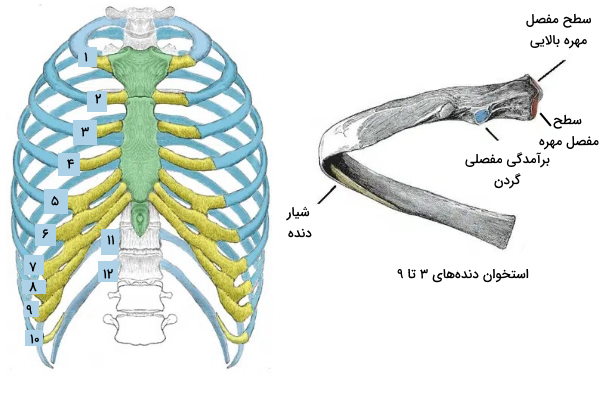

دندهها مجموعه ۶ جفت استخوان هستند که قفس آناتومی قفسه سینه را تشکیل میدهند. هر یک از این استخوانها در پشت بدن با مهرههای سینهای مفصل تشکیل میدهند و بهوسیله غضروفهای دندهای به استخوان جناغ متصل میشوند. این استخوانها علاوه بر محافظت از قلب و ریه، به تغییر فشار حفره سینهای و تنفس کمک میکنند. ساختار دندههای ۳ تا ۹ با دندههای ۱، ۲، ۱۰، ۱۱ و ۱۲ تفاوت دارد.

- دندههای ۳ تا ۹: استخوان این دندهها از بخش سر، گردن و تنه یا شفت تشکیل شده است. دو جایگاه تشکیل مفصل در دو طرف برآمدگی سر وجود دارد که یکی از آنها با استخوان مهره همسطح و دیگری با استخوان مهره بالایی مفصل تشکیل میدهد. گردن بخشی بین سر و تنه است که برآمدگی آن با زائده عرضی استخوان مهره همسطح مفصل تشکیل میدهد. تنه بزرگترین بخش این استخوان، پهن و خمیده است. شیار داخلی شفت محل عبور رشتههای عصبی و رگهای سینهای است. بخش انتهایی دندههای ۳ تا ۷ با غضروف دندهای مستقل به تنه استخوان جناغ متصل میشود. استخوان ۷ و ۸ به غضروفهای دندههای قبلی متصل میشوند.

- دنده ۱: دنده ۱ از بقیه دندهها کوتاهتر است و فقط یک جایگاه مفصلی برای استخوان مهره همسطح خود دارد. دو شیار سطح بالایی این استخوان محل عبور رگهای زیر ترقوهای است. بخش جلویی این استخوان بهوسیله غضروف دندهای به استخوان مانبوریوم متصل میشود.

- دنده ۲: دنده ۲ از دنده یک باریکتر و بلندتر است. دو جایگاه مفصلی سر این استخوان با مهرههای ۲ (T2) و ۱ (T1) سینهای مفصل تشکیل میدهد. برآمدگی سطح بالایی این استخوان محل «شروع» (Origin) ماهیچه دندهای جلویی است. انتهای جلویی این استخوان بهوسیله غضروف دندهای به انتهای مانبوریوم متصل میشود.

- دنده ۱۰: سر این دنده مثل استوان دنده ۲ فقط یک جایگاه مفصلی دارد که در تشکیل مفصل با استخوان مهره همسطح شرکت میکند. انتهای جلویی این استخوان به غضروفهای دندهای بالایی متصل میشود.

- دنده ۱۱ و دنده ۱۲: گرد در این دو استخوان وجود ندارد و تنها جایگاه مفصلی که در سر وجود دارد با استخوان مهره همسطح مفصل تشکیل میدهد. انتهای جلویی این استخوانها آزاد است.